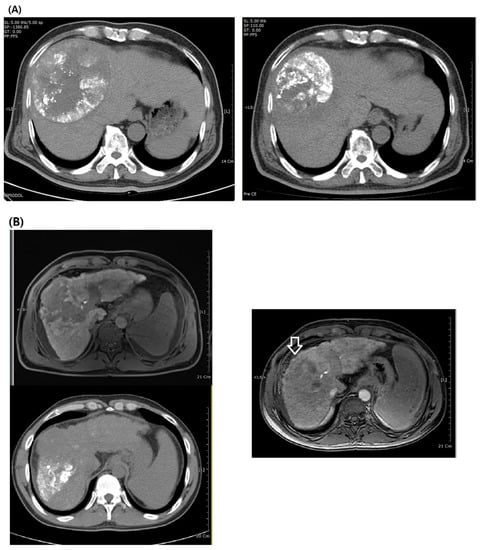

- Park, S.; Yoon, W.S.; Jang, M.H.; Rim, C.H. Clinical efficacy of external beam radiotherapy complementing incomplete transarterial chemoembolization for hepatocellular carcinoma. Int. J. Radiat. Biol. 2020, 96, 1541–1549. [Google Scholar] [CrossRef] [PubMed]